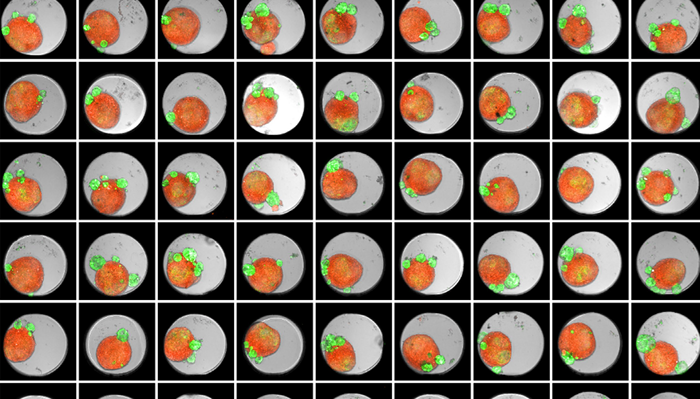

Thumbnail of an Akura 384™ well plate of 3D tumor co-culture microtissues - NCI-N87-GFP (green), NIH-RFP (red), Bright Field (gray)

Figure 1. Thumbnail of an Akura 384 well plate of 3D tumor co-culture microtissues - NCI-N87-GFP (green), NIH-RFP (red), Bright Field (gray). Image Credit: Yokogawa Life Science

Tumor spheroids were created by seeding an Akura 384 plate with a monodispersed mixture of GFP-expressing NCI-N87 (gastric carcinoma) and RFP-expressing NIH3T3-L1 (murine fibroblast) cells, which spontaneously formed spheroids through scaffold-free self-assembly over several days. After spheroid formation, selected wells containing tumor spheroids were treated with DMSO at 0.05, 0.5, or 5.0 μM Lapatinib for six days. The images were analyzed in 3D, with NCI-N87-GFP (tumor) and NIH-RFP (fibroblast) identified separately, and the volume of each spheroid measured.

This research allowed InSphero AG to accurately quantify pharmacological effects on their 3D models. The fully automated system enhanced multi-condition simultaneous testing, leading to increased workflow efficiency. By implementing the HCA platform, InSphero AG provides seamless solutions, from in vitro 3D models to evaluations.